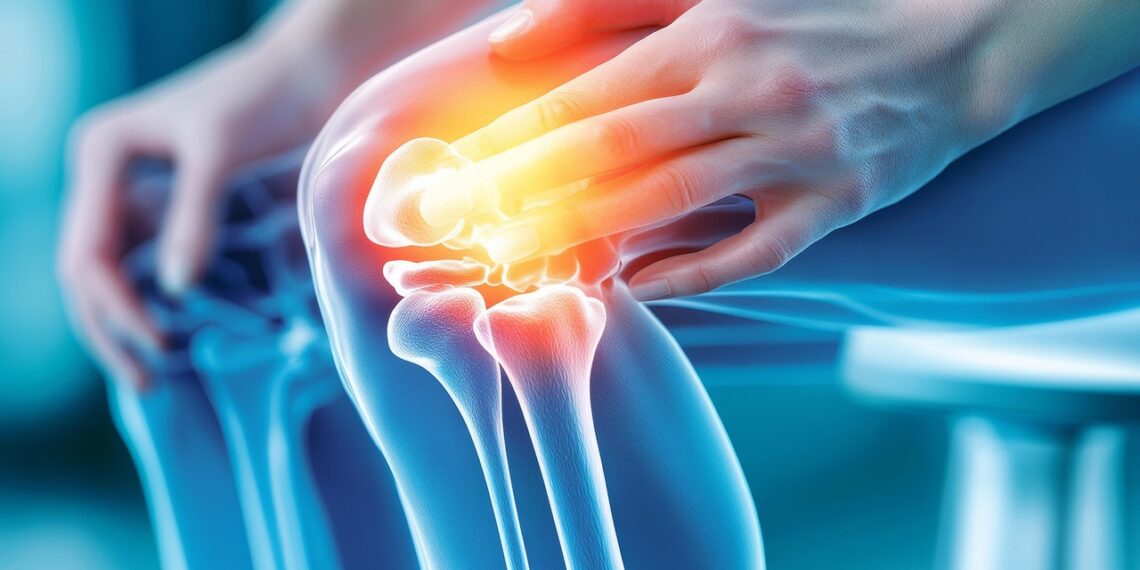

관절염과 위염이 통증을 동반하는 이유는 명백하다. 염증 때문이다. 염증은 다양한 원인으로 세포나 조직이 손상되었을 때 발생하며, 통증은 이런 위험을 알리는 우리 몸의 경고신호인 셈이다. 즉, 염증을 예방해야 통증을 막을 수 있으며, 염증을 막으려면 세포가 손상되는 것을 막아야 한다는 것이다.

세포가 손상으로 관절과 위(胃)의 방어막이 사라지면 통증이 생긴다.

관절과 위(胃)는 염증이나 통증으로부터 스스로를 보호하는 방어막들을 가지고 있다.

로테오글리칸은 관절이 받는 충격을 스프링처럼 흡수해서 연골을 보호하고, 위점액은 위점막층을 둘러싸 강한 위산으로부터 위를 보호한다. 그런데, 나이가 드는 등의 다양한 원인이 의해 세포가 손상되면 관절과 위를 보호하던 방어막의 양이 감소하고 염증과 통증이 발생하게 된다.

연골세포가 손상되면 관절의 주성분인 프로테오글리칸이 생성되는 속도보다 분해속도가 빨라져 연골조직이 파괴되면서 관절염이 진행된다. 또한, 위점액세포가 손상되면 위점액의 생성이 감소되고 위를 보호하던 보호막이 파괴되면서 염증과 통증의 발생으로 이어진다.